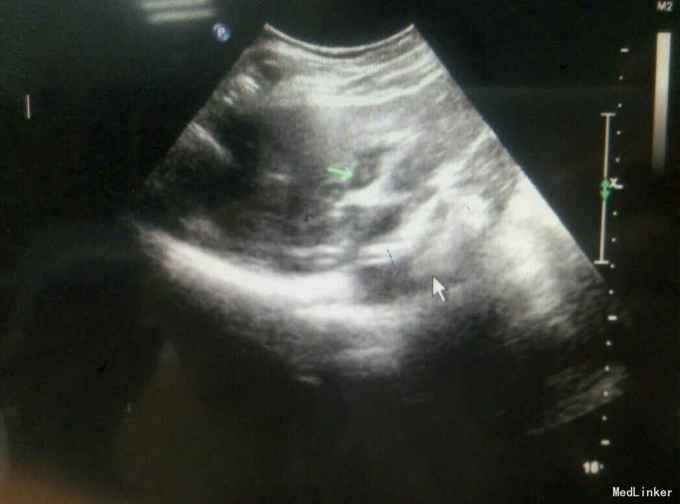

患者,女,43岁,左乳癌术后2年余,发现肝脏占位3天

查体:未及明显异常 辅助检查:腹部彩超发现肝脏多发占位,考虑转移,腹部增强CT:肝脏多发结节,考虑乳腺癌肝转移

随访与讨论:患者入院时肝功能就偏高,也算是一个肝功能受损征相,而且彩超检查发现门静脉有癌栓形成,说明比较晚期,预后不良,所以采取姑息性辅助化疗,希望可以减轻患者病痛。当然同时也要排除其他地方转移,以采取相关治疗措施。